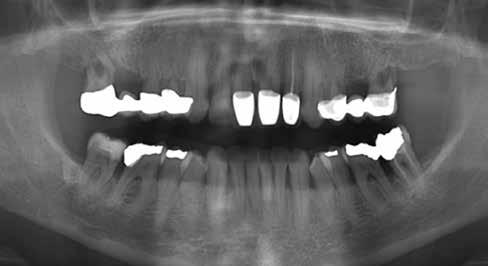

1. a–d. ábra: Műtét előtti állapot mind a négy páciensnél. 1. eset (a). 2. eset (b). 3. eset (c). 4. eset (d).

Az alábbi esettanulmányhoz négy pácienst választottunk ki (1. táblázat). Minden esetben egy, vagy több fog pótlására volt szükség, amelyhez kerámiaimplantátumokat használtunk. Valamennyi páciens általános egészségügyi állapota jó volt.

Vizsgálatok

A pótlásra szoruló fogat, vagy fogakat minden esetben legalább egy évvel a fogpótlást megelőzően eltávolítottuk. Ezen esetek egyikében sem végeztünk alveolus vagy állcsontgerinc prezervációt az eltávolítás során, illetve minden páciens jó szájhigiéniával rendelkezett. Egy kivételével minden páciensnél radiológiai analízist végeztünk CBCT-vel, amelyet

digitális implantátumtervezés követett (SICAT és Sidexis, mindkettő Dentsply Sirona; 1. ábra).